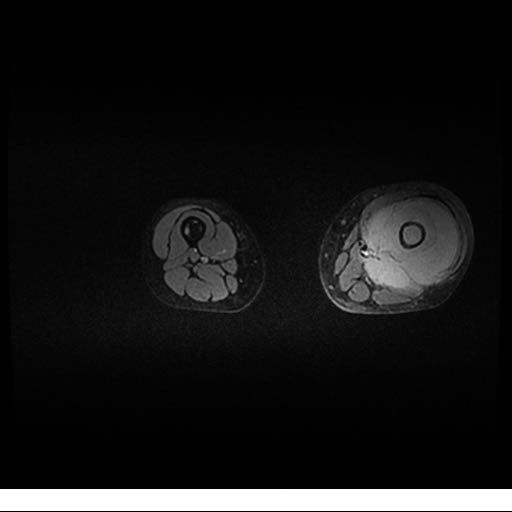

Se realiza estudio de MRI de muslo izquierdo en diferentes planos, con secuencias de Spin Echo, GRE; ponderadas a T1 y a T2, se utilizan pulsos de saturación de grasa y se administra medio de contraste IV a base de Gadolinio en base al peso del paciente.

La diáfisis femoral izquierda muestra reacción perióstica importante, se extiende desde el cuello del fémur, invade trocánteres, diáfisis femoral, medial y distal, es compatible con un proceso infeccioso óseo, el complejo muscular del muslo se ve edematizado.

Hallazgos en Resonancia Magnética (RM)

La resonancia es la modalidad de elección para valorar la extensión intramedular y la infiltración en tejidos blandos, brindando una imagen más detallada del compromiso tumoral. Los hallazgos característicos incluyen:

Lesión de señal heterogénea en secuencias T1 (hipointensa) y T2/STIR (hiperintensa), que refleja necrosis, hemorragia y contenido celular diverso.

Realce intenso y heterogéneo tras la administración de contraste (gadolino), lo que indica vascularización tumoral.

Compromiso de la médula ósea adyacente y de estructuras vecinas, como músculos y neurovasculatura.

Posible presencia de edema óseo y necrosis central.